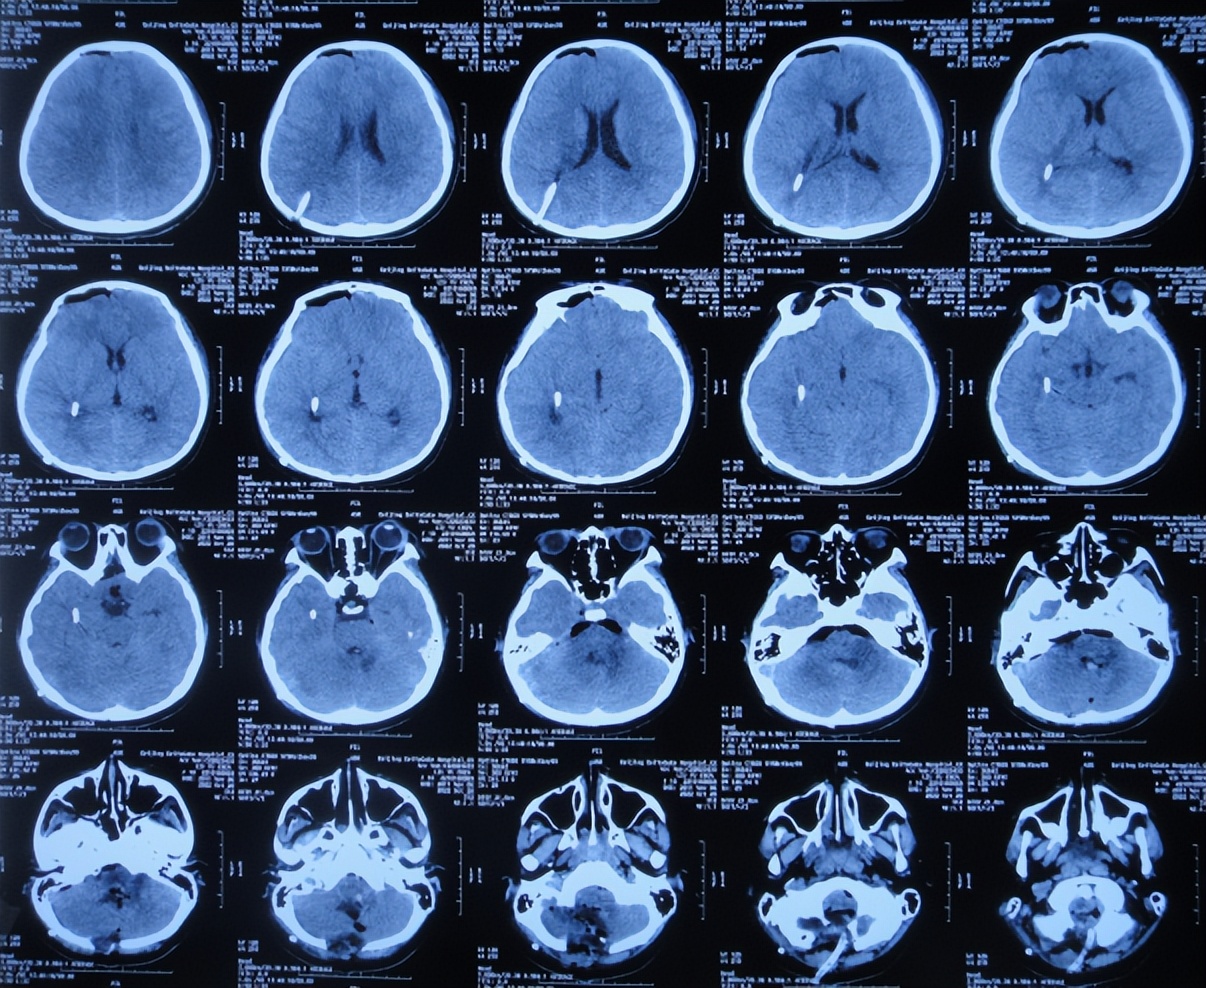

2022年10月30日(住院治疗14天),头痛加重,查颅脑CT示脑室又有扩张( 图-12 );肺部感染( 图-13 )。

图-12: 2022年10月30日颅脑CT

2022年10月31日(住院治疗15天),进行了脑室腹壁外引流管调整术( 图-14 )。

图-14: 2022年10月31日颅脑CT

2022年12月12日(住院治疗57天),颅脑CT示脑室引流术后状态( 图-15 ),给予夹闭引流管。

图-15: 2022年12月12日颅脑CT

但夹闭5天后即2022年12月17日,患儿出现不适,查颅脑CT示脑室有扩张( 图-16 ),打开引流管。

图-16: 2022年12月17日颅脑CT

2022年12月20日(住院治疗65天),查头颅CT示脑室缩小( 图-17 ),肺部CT示感染好转( 图-18 )。

图-17: 2022年12月20日颅脑CT